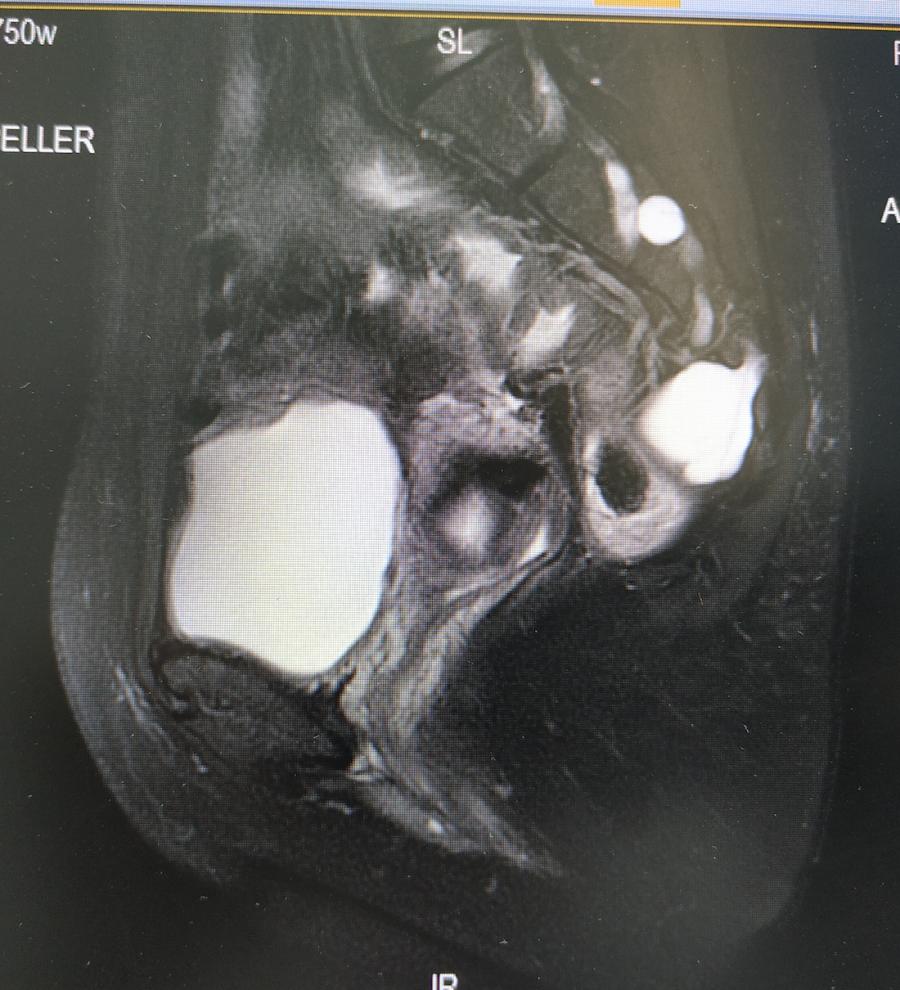

盆腔MR结果提示:

1、骶管、双侧骶椎间孔、骶骨及梨状肌前方盆腔内多发囊状信号影,考虑神经根袖囊肿,建议进一步检查;

2、右侧髋臼异常信号影,考虑血管瘤可能性大;

3、双侧腹股沟浅区小淋巴结显示。

神经外科会诊意见:患者查MR提示骶管、双侧骶椎间孔、骶骨及梨状肌前方盆腔内多发囊状信号影,考虑神经根袖囊肿。患者现无相关神经压迫等症状,建议定期复查,暂不考虑手术治疗。